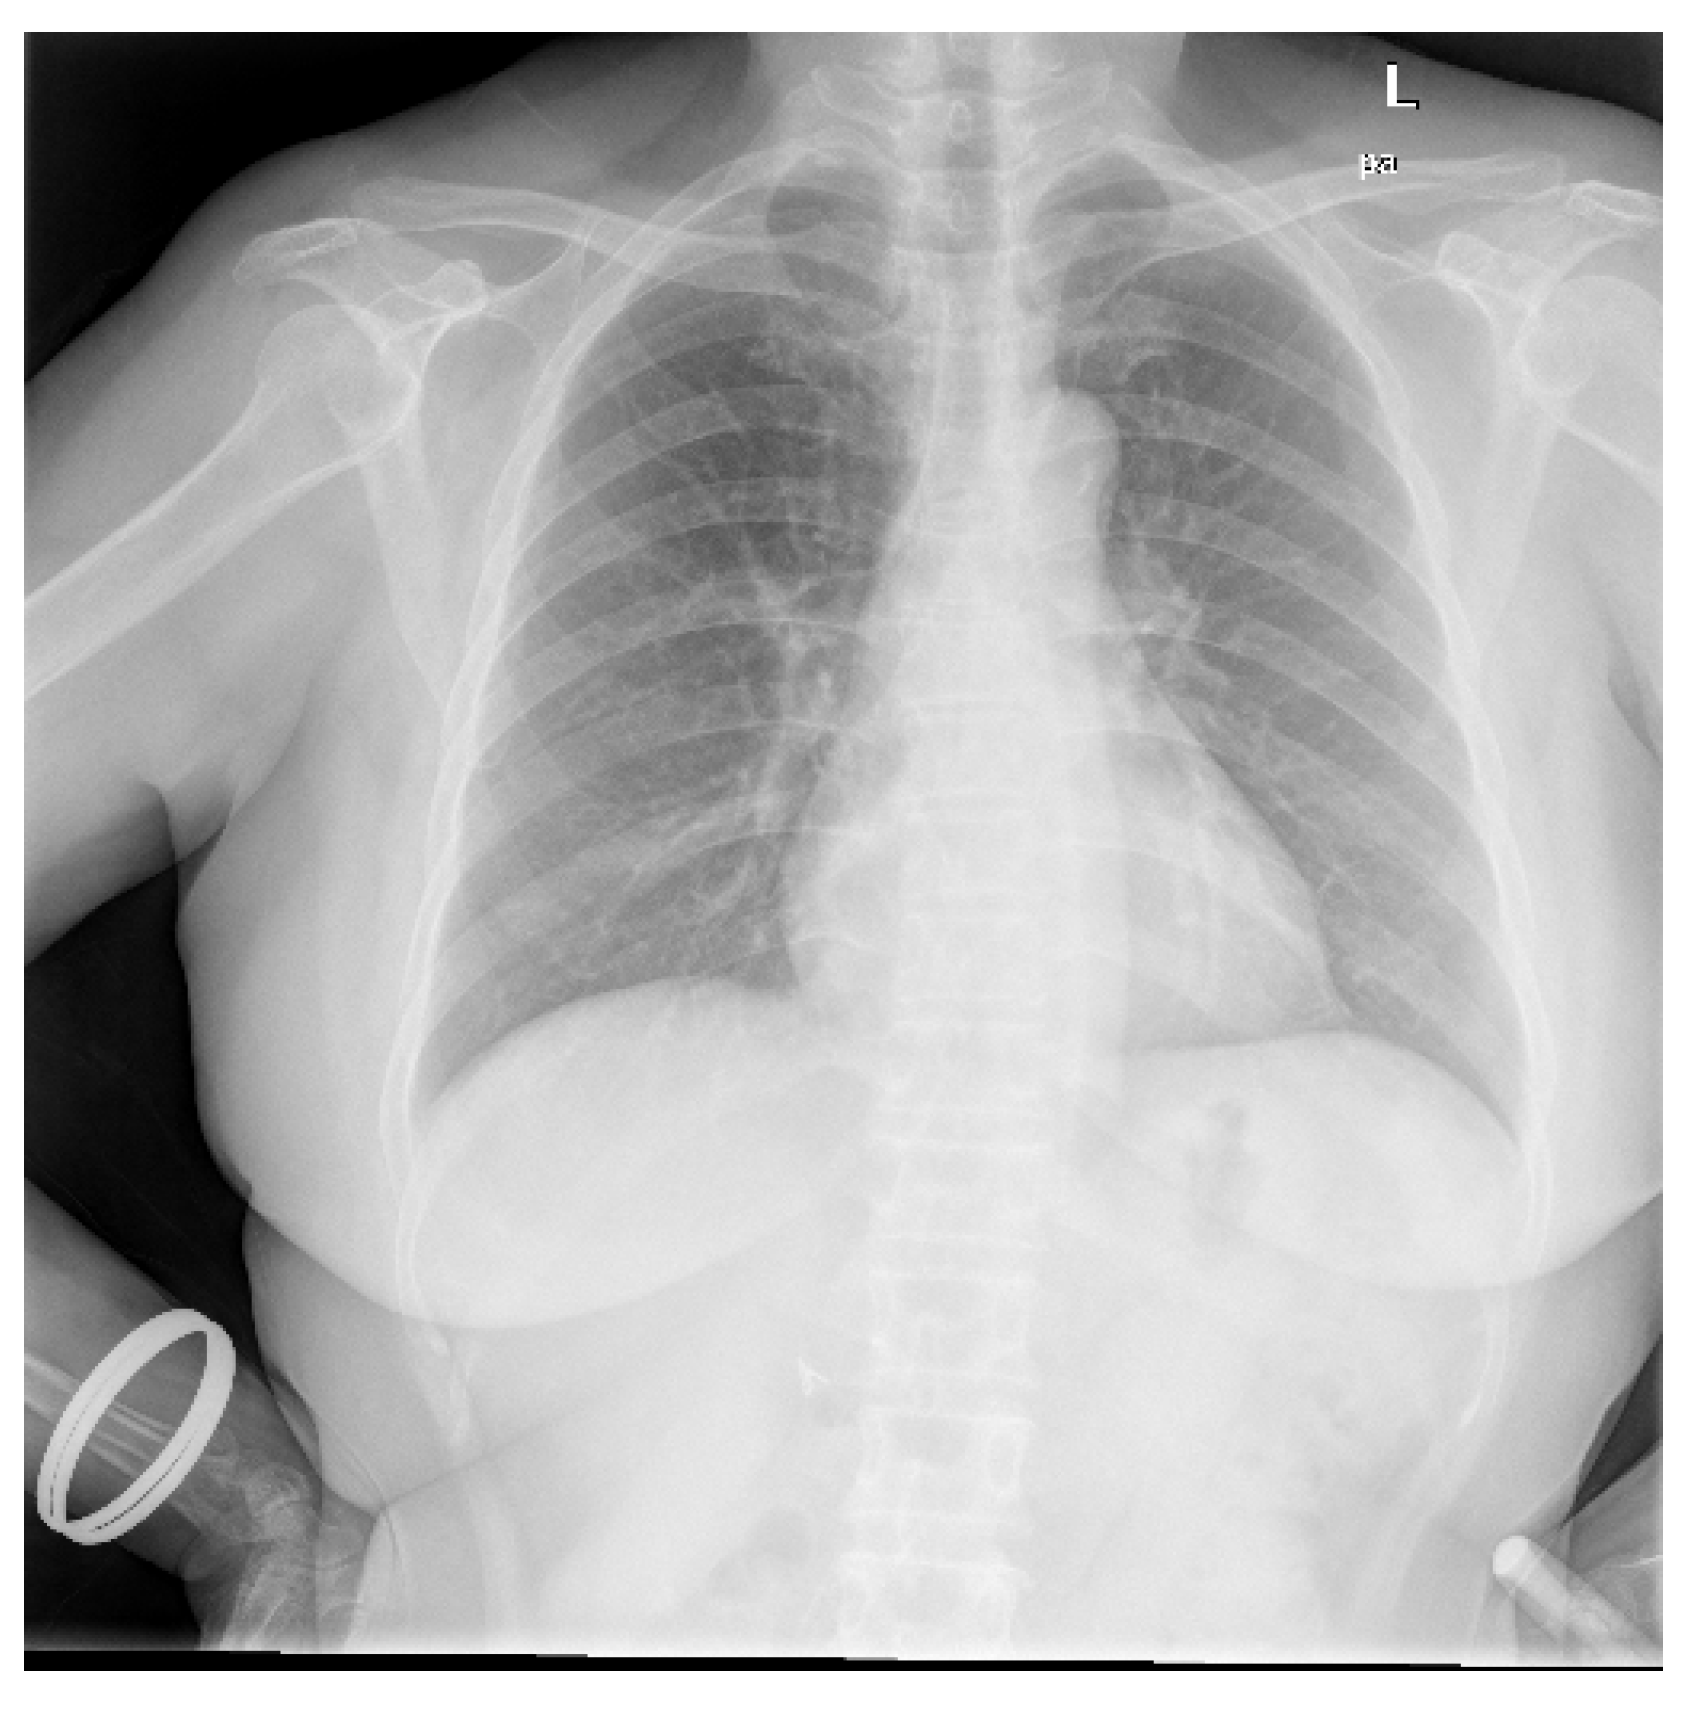

Data utilized in this research were collected from various secondary sources. The chest radiograph was collected from the Department of Health and Human Services, Montgomery County, MD, USA [27]. This dataset consists of 138 frontal chest X-ray images, out of which 80 are normal cases and 58 are cases with manifestations of TB. Moreover, the images are in Portable Network Graphics (PNG) format as 12-bit gray-level images, and the size of each X-ray image is either 4020 × 4892 or 4892 × 4020 pixels. The sample image, along with its GT segmented image from the chest radiograph dataset, is shown in Figure 2 and Figure 3. Further, 23 CT images with segmented CT from VESSELS12 Challenge and 42 CT images with segmented CT from LUNA16 Challenge were downloaded to form a CT dataset. Then X-ray images (DRR) were simulated from CT images. This simulation generated both posterior-anterior (P-A) chest radiographs and lateral chest radiographs. Besides, the lung volume ground truth is available in this dataset, which includes lung statistics such as lung area and lung volumes. Table 1 shows the data used in our study with data source and type. In this research, the number of training samples is small, so data augmentation is performed by rotating, flipping, and scaling the intensity.

Figure 2.

Sample chest radiograph from CXR dataset.